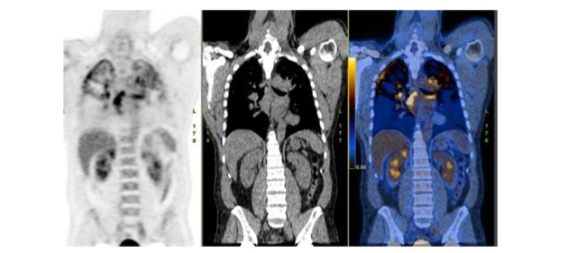

In patients with sarcoid, ¹⁸F-FDG has emerged as an important modality, with a sensitivity and specificity of 89% and 78%, respectively, for diagnosis (Figure 18)⁶⁷.

Figure 18.

Cardiac sarcoid. On the myocardial perfusion image (left), there is a defect (arrow) in the mid anterior wall of the left ventricle. On the ¹⁸F-FDG image (right), there is increased activity (arrow) in the same region. This pattern is virtually diagnostic of cardiac sarcoid.

Quantification of myocardial ¹⁸F-FDG uptake is useful for assessing the severity of myocardial inflammation, and monitoring response to therapy⁶⁸. A decrease in myocardial uptake on serial studies correlates with improved left ventricular ejection fraction⁶⁹. A lack of decreased uptake on serial scans correlates with a significant increase in death, hospitalization for heart failure, heart transplantation, and ICD therapies⁷⁰. Serial studies are useful for guiding immuno-suppressive therapy⁷¹.